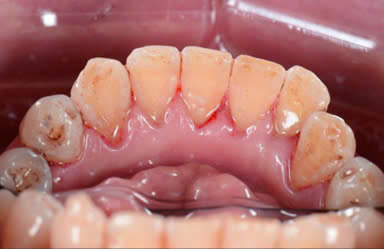

Một số hình ảnh trước và sau khi lấy cao răng:

Case 1: